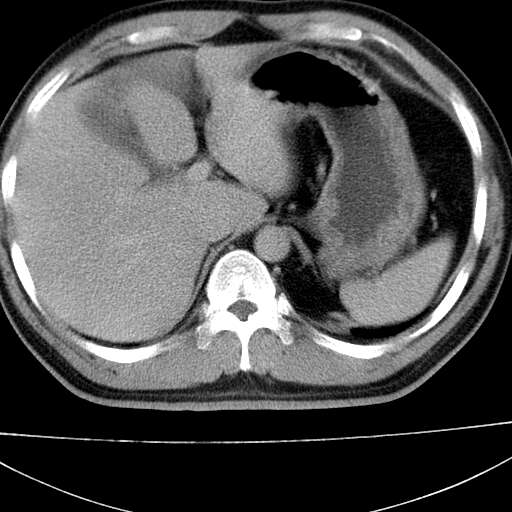

标题: CT21921:腹膜后腔肿物。患者男39Y。体检。增强扫描时间欠准 [打印本页]

标题: CT21921:腹膜后腔肿物。患者男39Y。体检。增强扫描时间欠准

膈疝

左肋隔角占位,考虑胸膜间皮瘤

考虑左肺下叶后基底段肺隔离症?胸膜间皮瘤?

左下肺隔离症,可见从胸主动脉发出异常血管供应